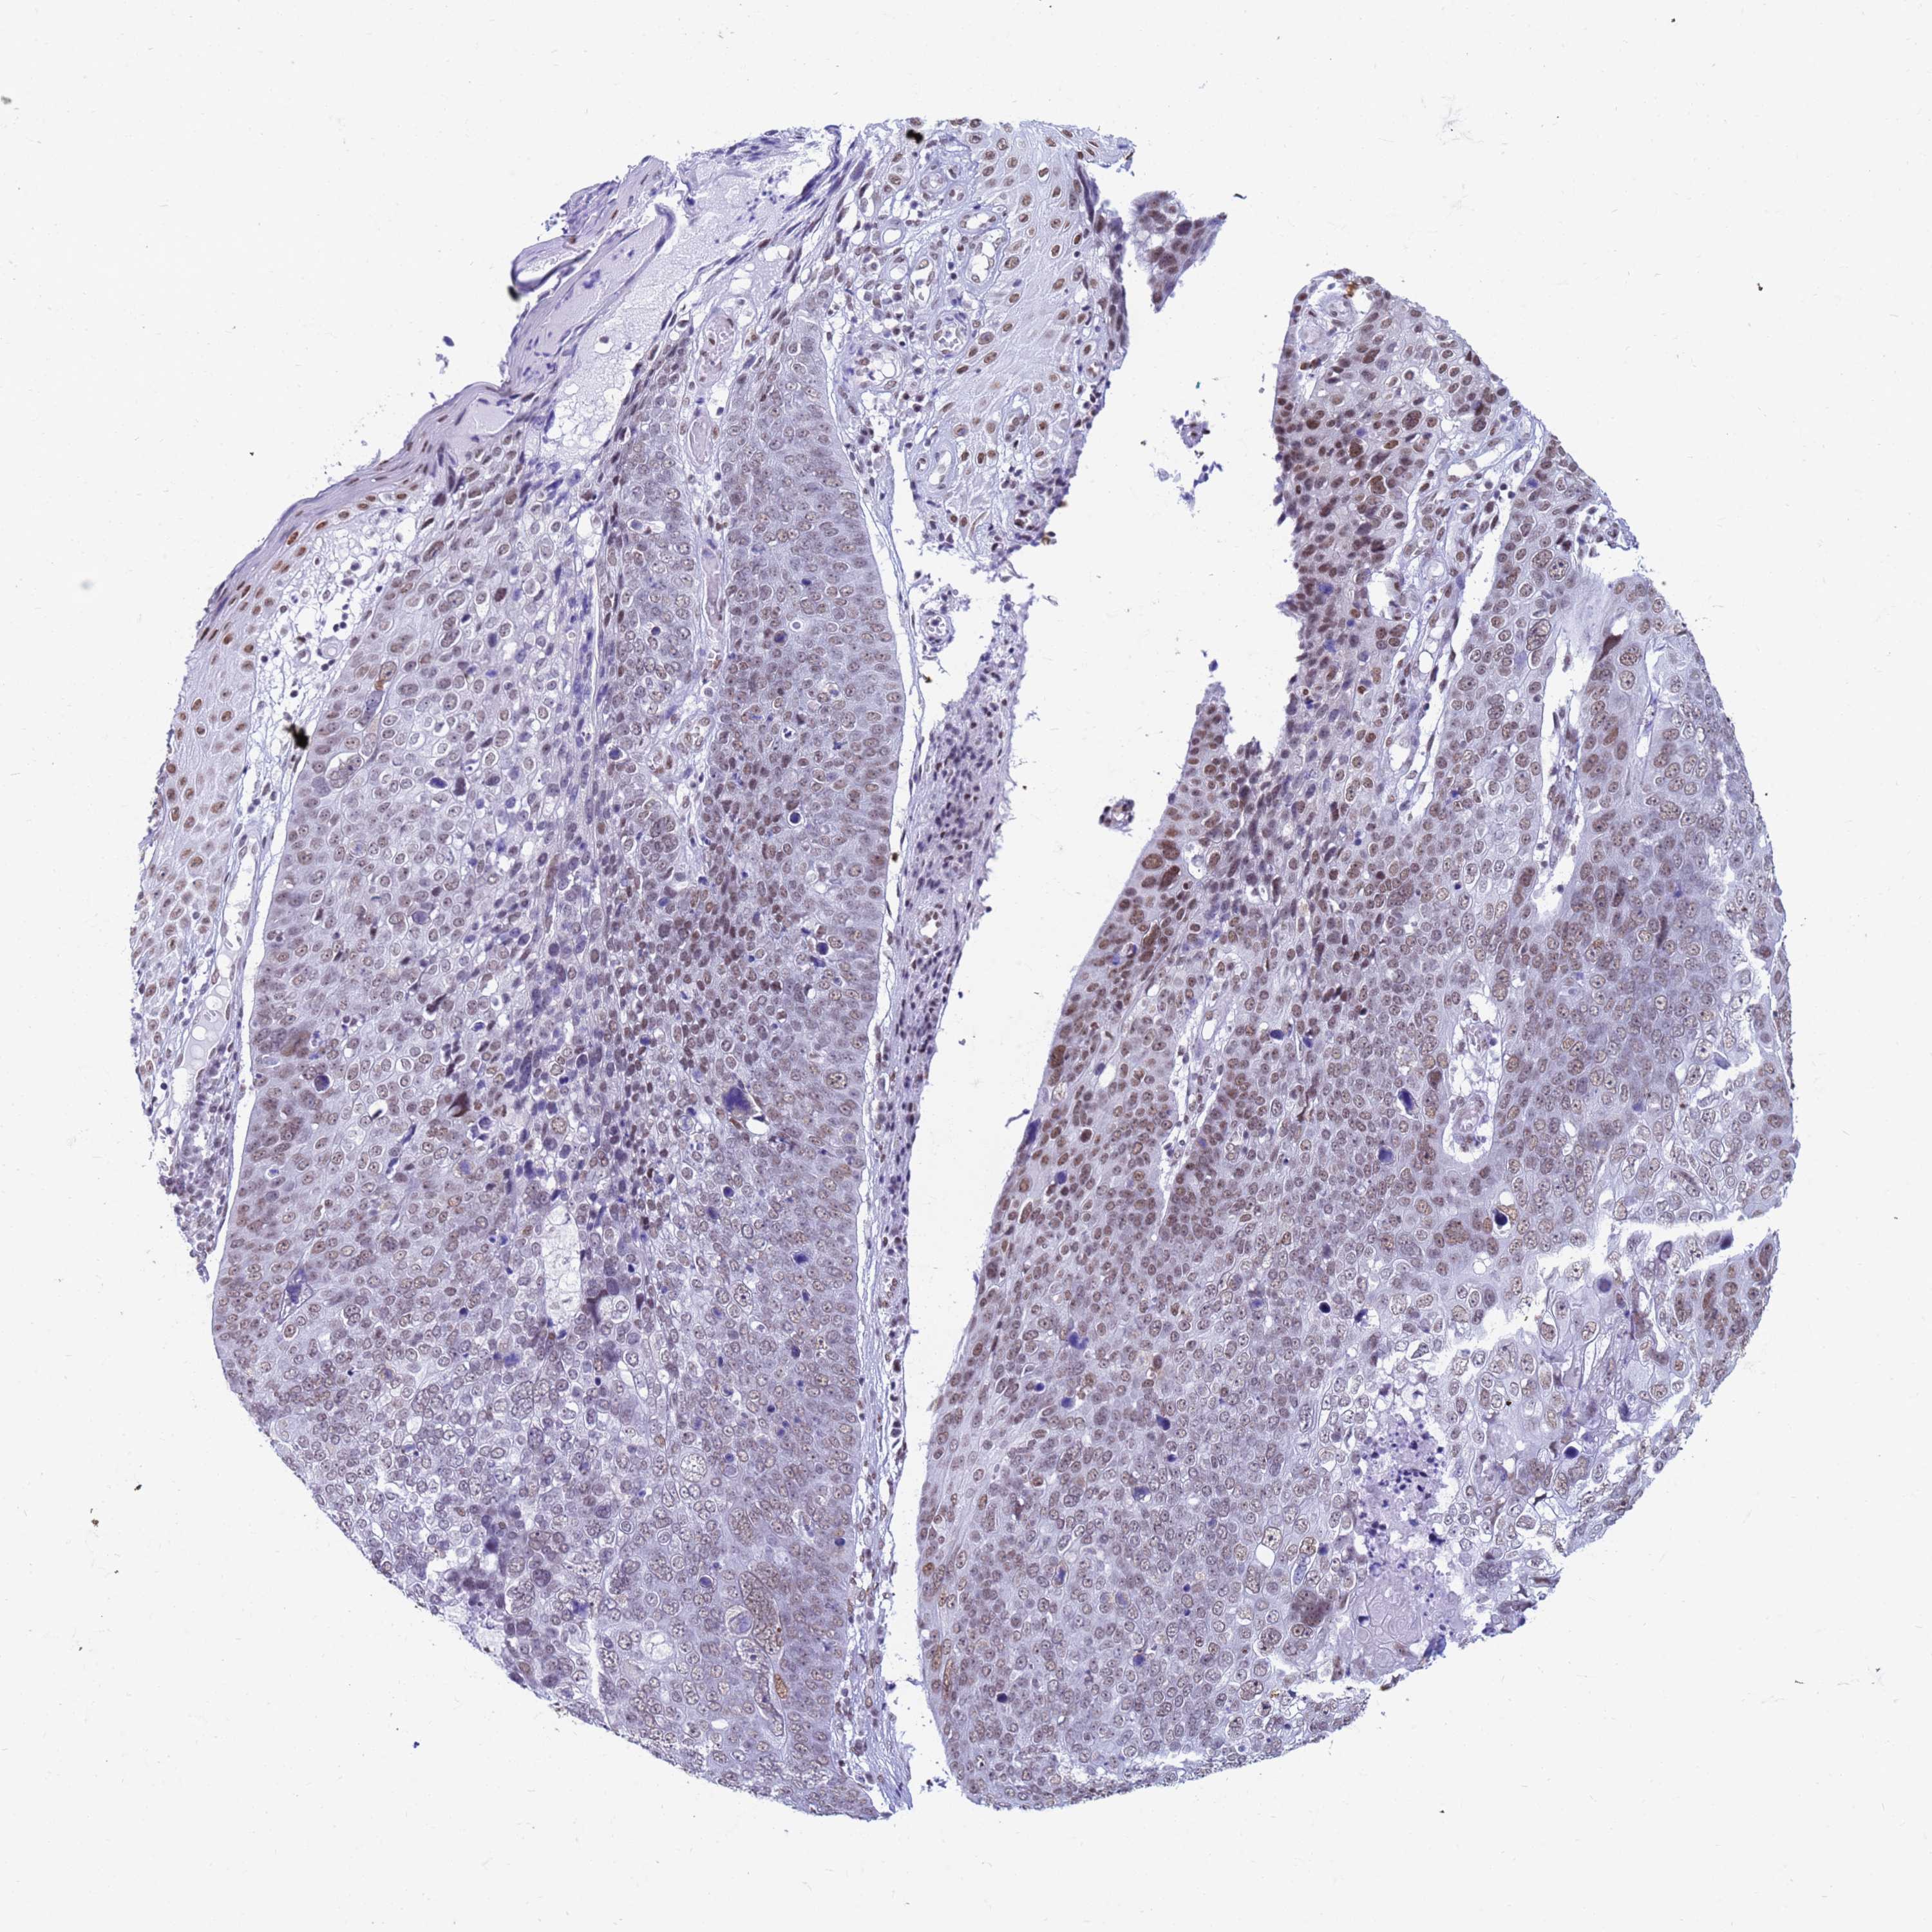

SKIN CANCER - Protein expressioni

A mouse-over function shows sample information and annotation data. Click on an image to view it in a full screen mode. Samples can be filtered based on level of antibody staining by selecting one or several of the following categories: high, medium, low and not detected. The assay and annotation is described here.

Antibody staining in the annotated cell types in the current human tissue is reported as not detected, low, medium, or high, based on conventional immunohistochemistry profiling in selected tissues. This score is based on the combination of the staining intensity and fraction of stained cells.

Each image is clickable and will lead to virtual microscopy that enables deeper exploration of all samples and also displays staining intensity scores, fraction scores and subcellular localization as well as patient and tissue information for each sample.

Antibody HPA050610

Squamous cell carcinoma, NOS